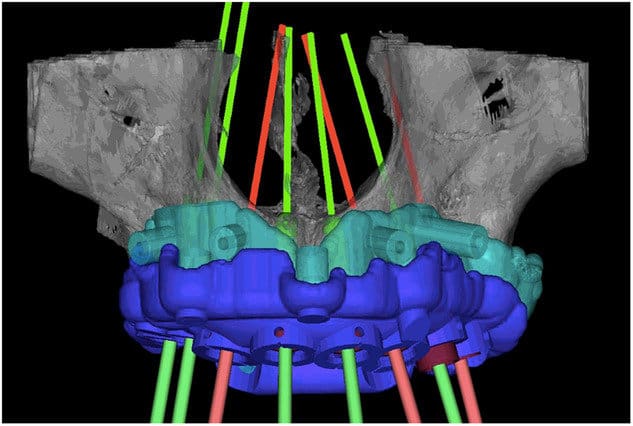

Diseño de férula para colocación de implantes de forma guiada en arco completo. Recomendada para casos de 4-8 implantes.